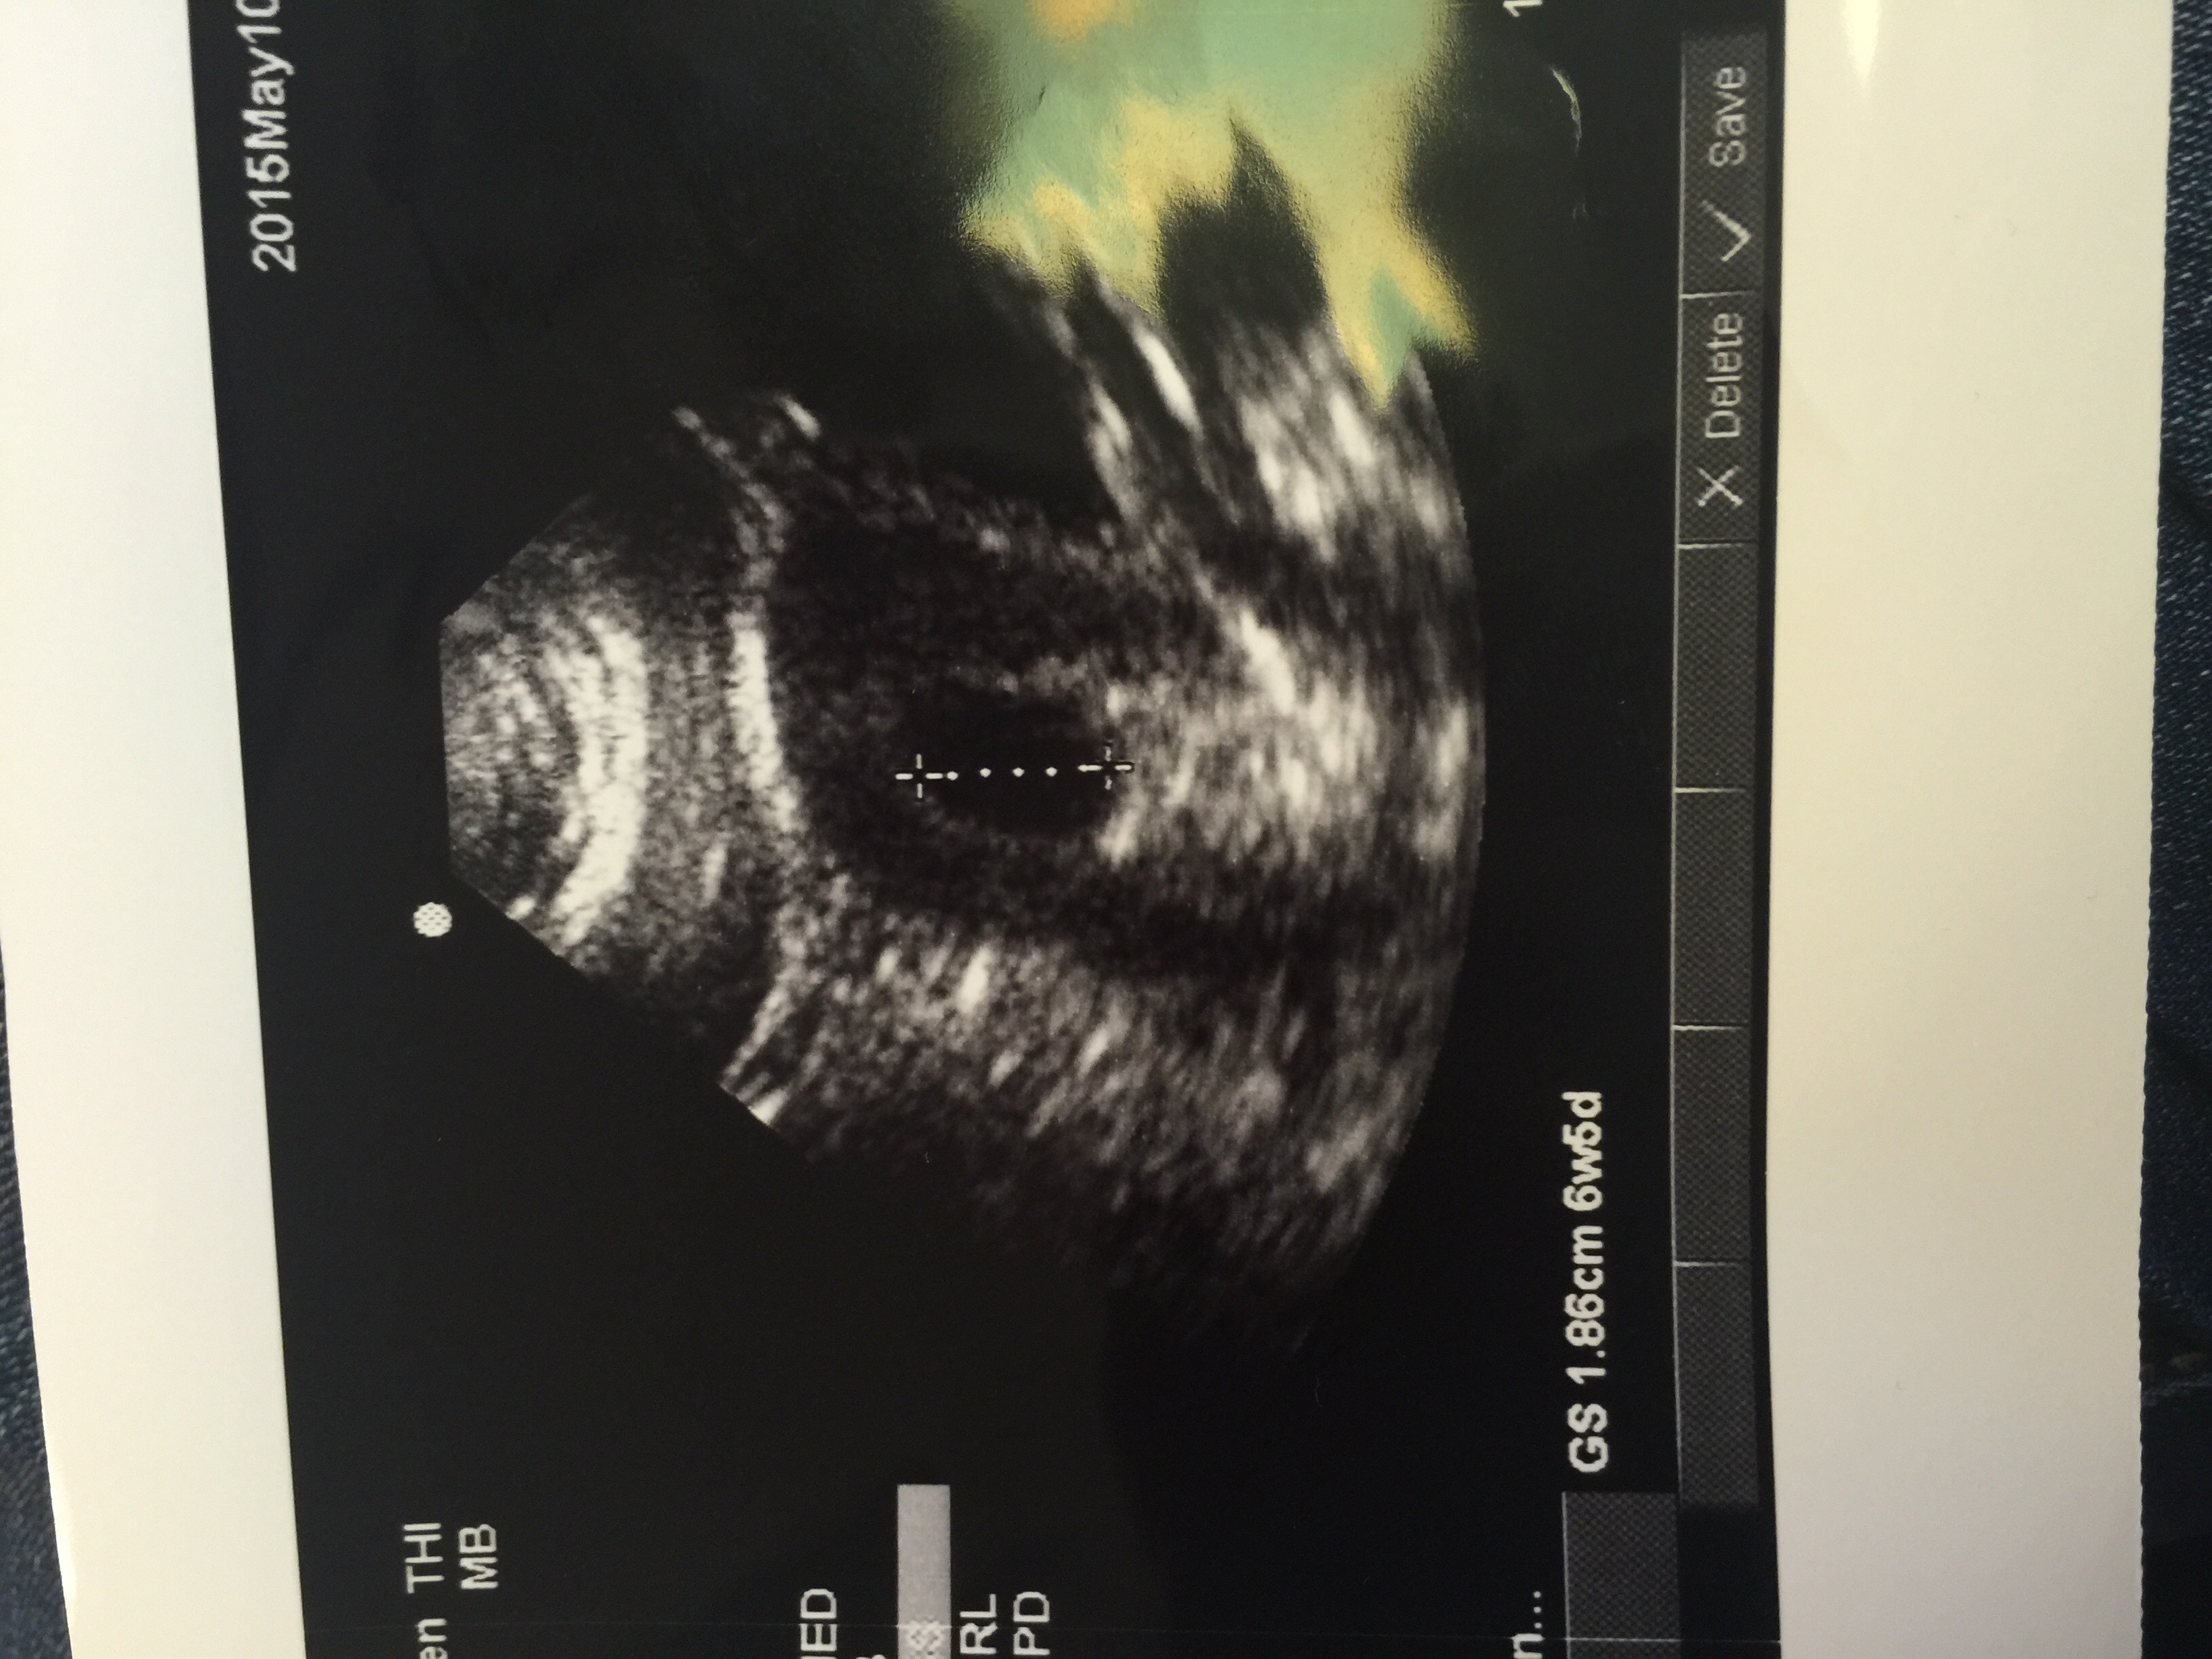

This was a transabdominal ultrasound.

Our little one today! 6w1d

108HB